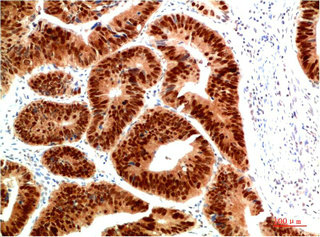

Immunohistochemical analysis of paraffin-embedded Human Brain Tissue using HSP40 Rabbit pAb diluted at 1:200